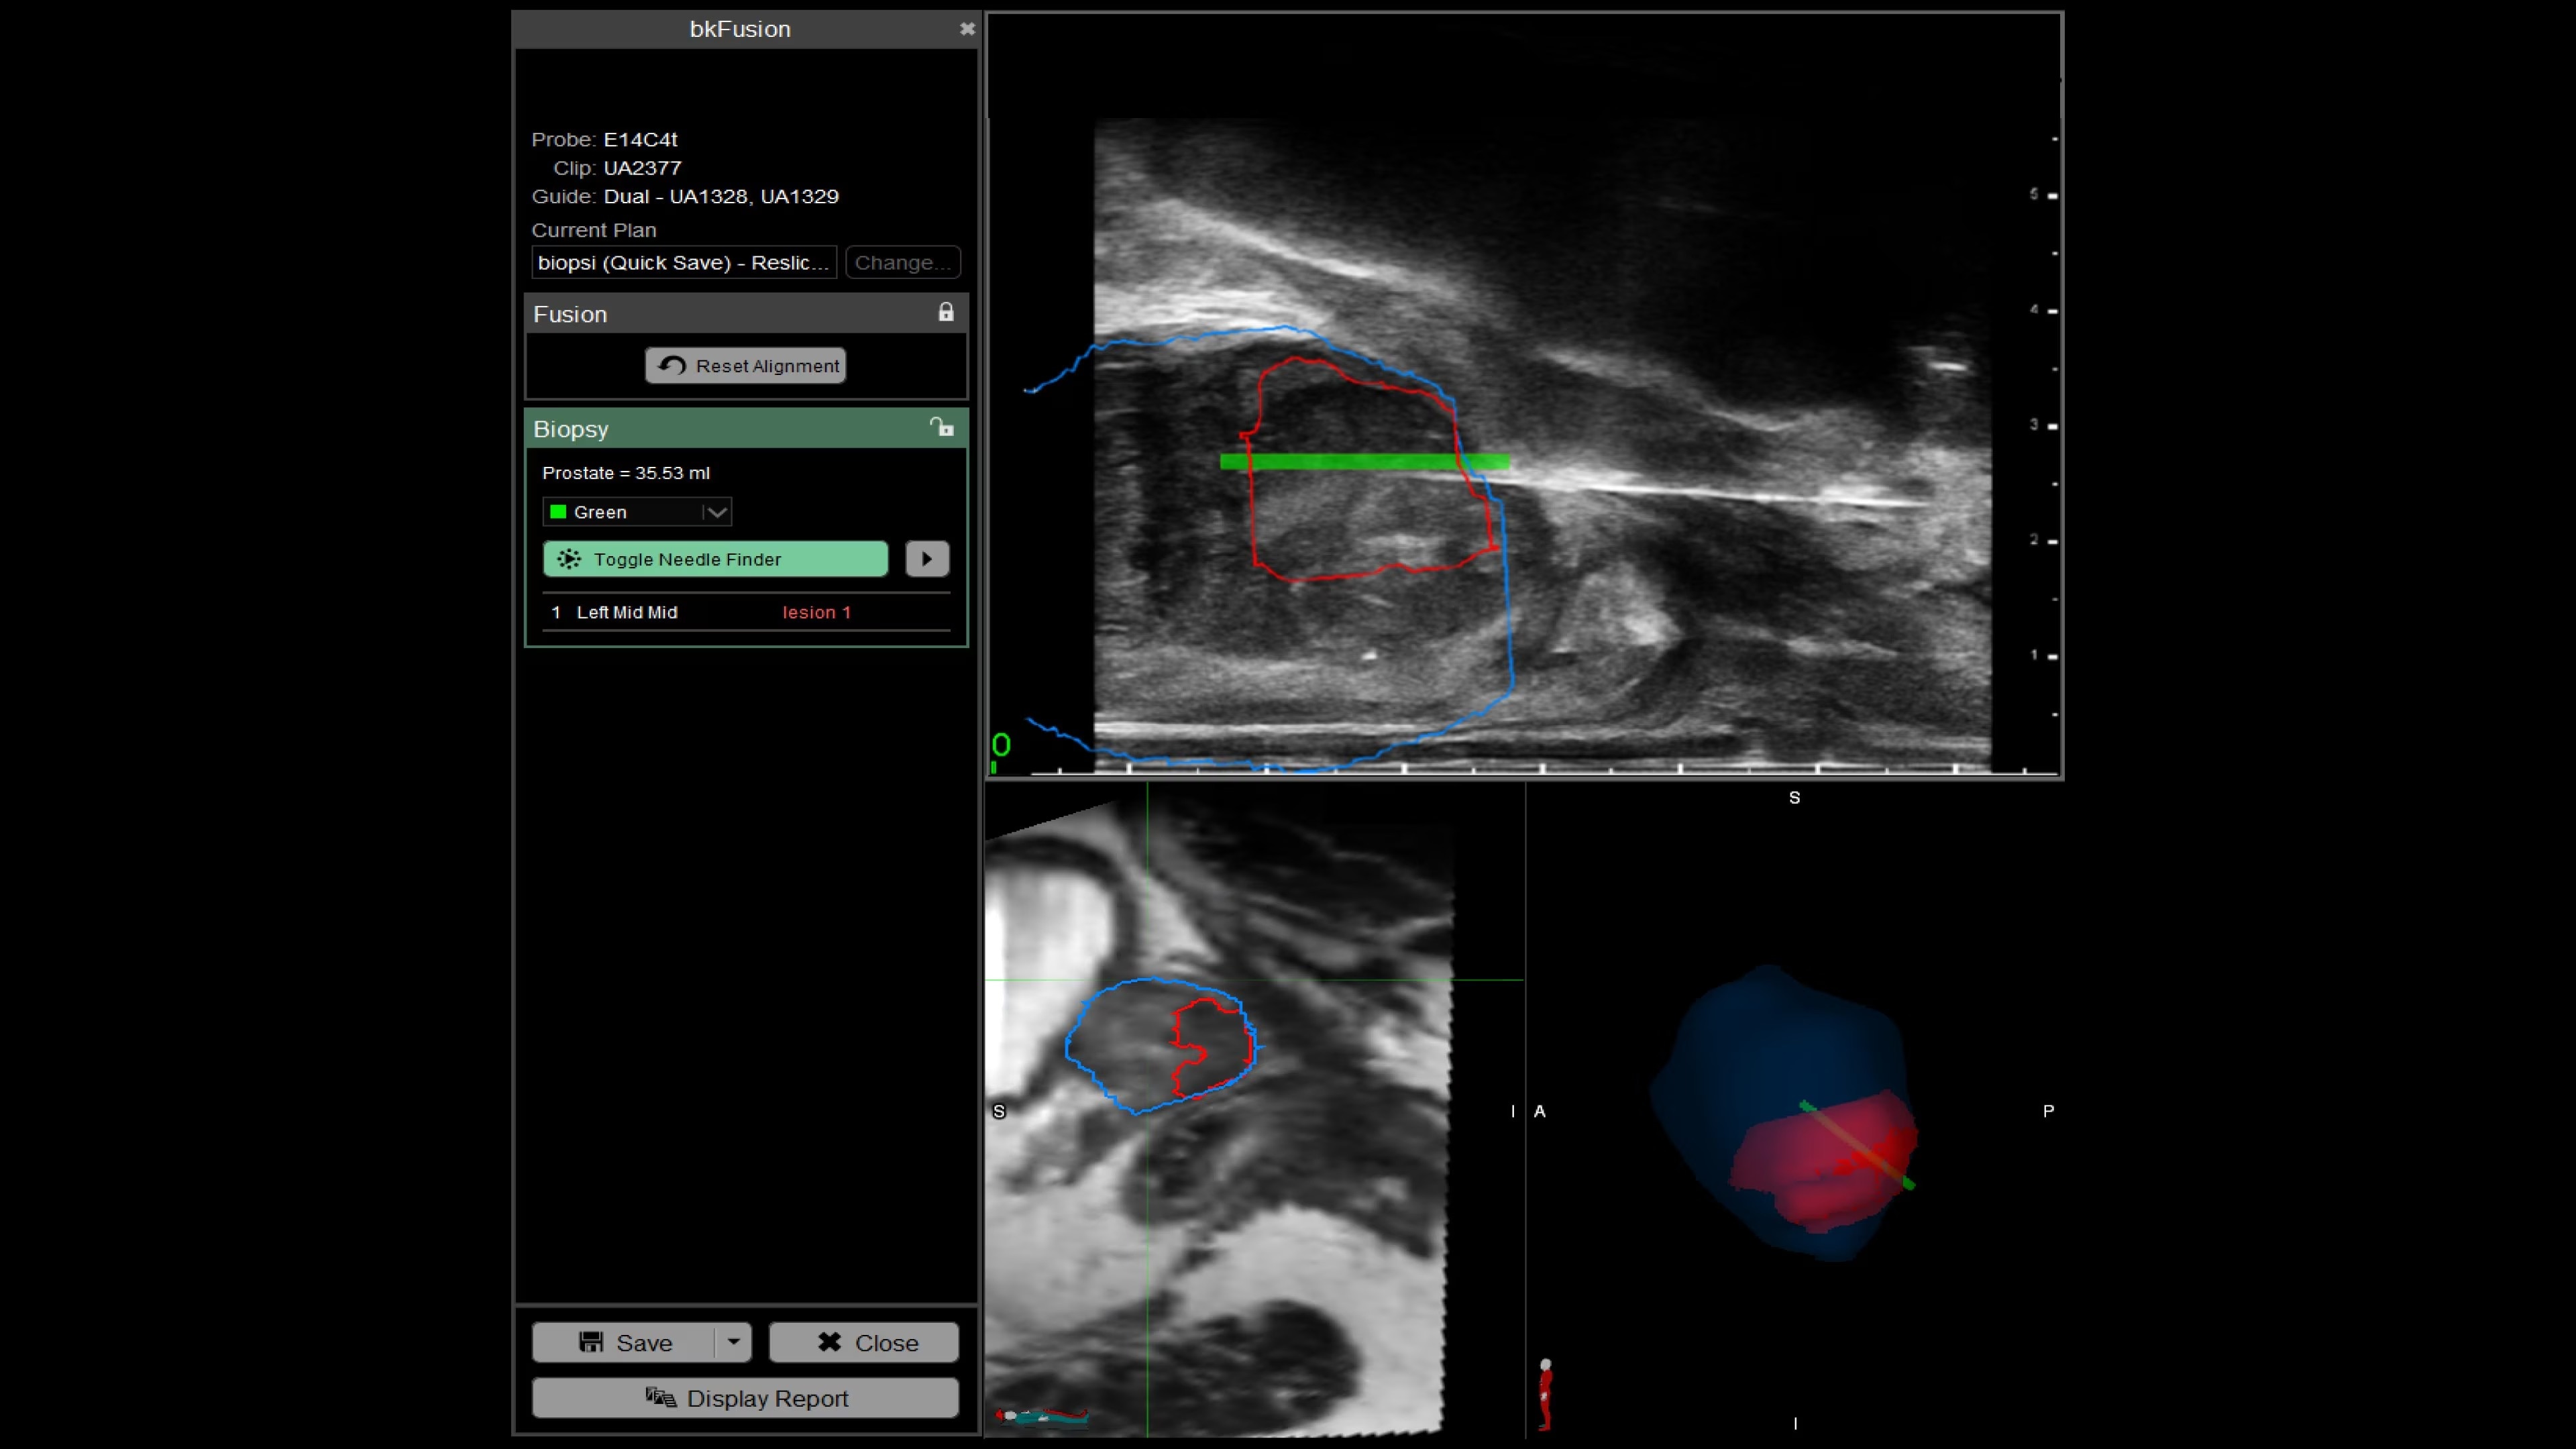

With bkFusion, confidently target your biopsy with clear visualization of organ borders to detect registration errors or deformations in real-time. bkFusion, MRI-ultrasound fusion biopsy solution features proprietary imaging algorithms developed with high spatial, temporal, and contrast resolution for advanced visualization.

bkFusion has proven to accurately detect 84% of PIRADS 3-5 lesions and up to 81% GG>=2 cancer.¹

Enhance biopsy accuracy with Predictive Fusion®

Predictive Fusion® is the proprietary registration method allowing you to imediately see any errors in the overly of MRI and ultrasound images before and during the procedure. Utilizing rigid 2D slice registration, it eliminates distortion in merging 3D shapes, ensuring precise MRI-ultrasound fusion. If changes are needed, make simple, one-touch, micro-adjustments to updte the registration without calibration steps or 3D sweeps. Enhance your prostate biopsy accuracy with this advanced technology.